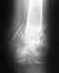

перелом голени обеих костей со смещением отломков в нижней трети

Добрый день Уважаемые доктора !!!Получил перелом обеих костей голени со смещением в нижней трети .Лечение 39дней вытяжка +гипс на 2 месяца по эпикризу.Но вызывает сомнения снимки .Хорошо ли стоят отломки и срастётся ли перелом при таком стоянии отломков.И примерные сроки срастания такого перелома?Вот снимки после гипсования.